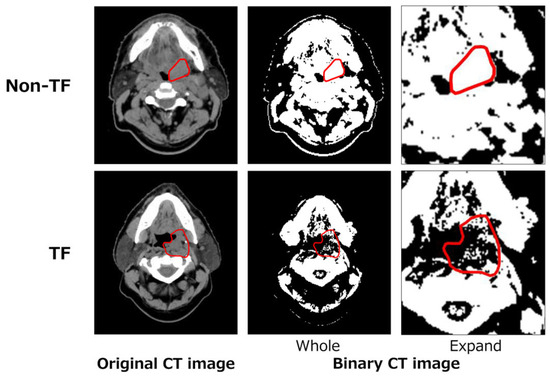

2.3.2. Local Binary Pattern (L) Feature

2.3.3. Topological (T) Feature

2.3.4. Deep (D) Feature